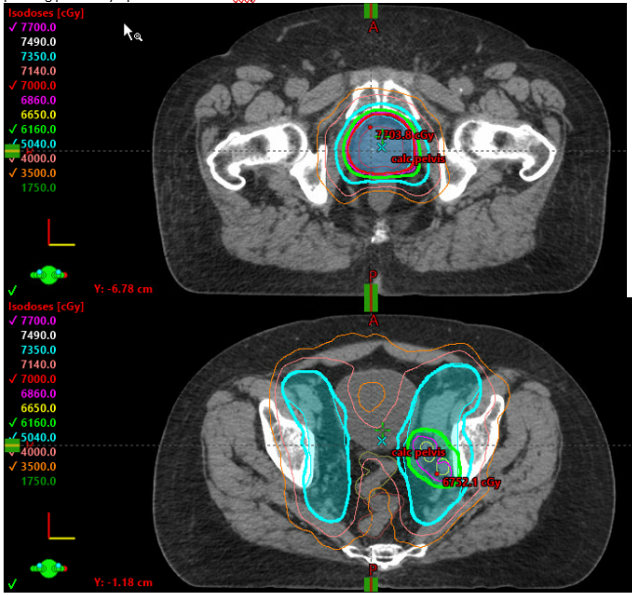

Gleason 6, Low Risk, Watchful waiting, SBRT toxicity, SIB, bladder cancer, low pelvis, hypofractionation, defining target, PSMA, prostate cancer, pT3aN0M0, rpT3acN1M0

Gleason score, active surveillance, periodic biopsy, prostate gland, pelvis, SIB, radiation-induced fibrosis, brachial plexus, head and neck, scleroderma, SBRT, TNM staging, bladder cancer, ASTRO, PSMA PET imaging, salvage prostatectomy, PSA

ADT, androgen deprivation therapy, LHRH antagonist, PSMA PET scan, definitive radiation, local salvage treatment, salvage brachytherapy, prostate cancer, PSA, genomic testing, brachytherapy, Gy, lymph nodes, pelvis, high risk intact patients, pelvic radiation, Mack Roach trials, salvage SBRT, loc...